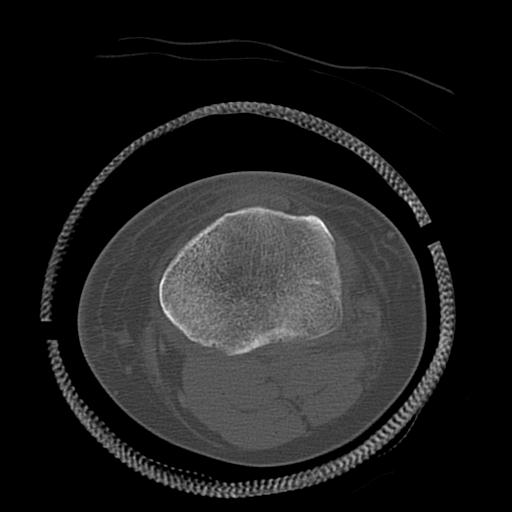

49554 3/13 膝 4R 3/16 4R 1/18 2R 78歳男性 膝蓋骨骨折